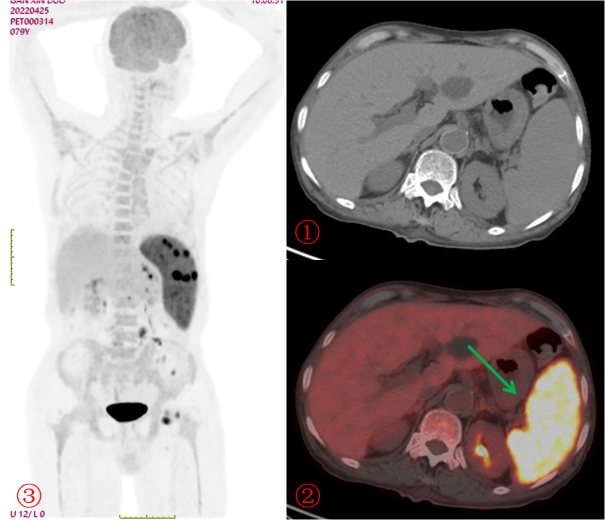

老年男性,發(fā)熱半月,全身CT未見確切異常。PET/CT示脾臟增大伴代謝明顯不均質(zhì)增高(圖2?綠箭),腹盆腔部分略大淋巴結(jié)伴帶代謝增高,診斷為淋巴瘤,病理證實為小B細胞淋巴瘤。